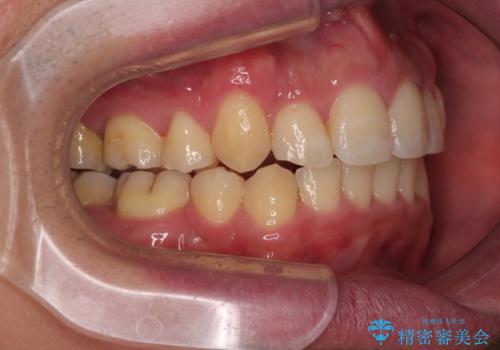

上下前歯の前後差が非常に大きく、3年以上の治療期間が予想されましたが、無事に3年間ちょうどで仕上げることができました。